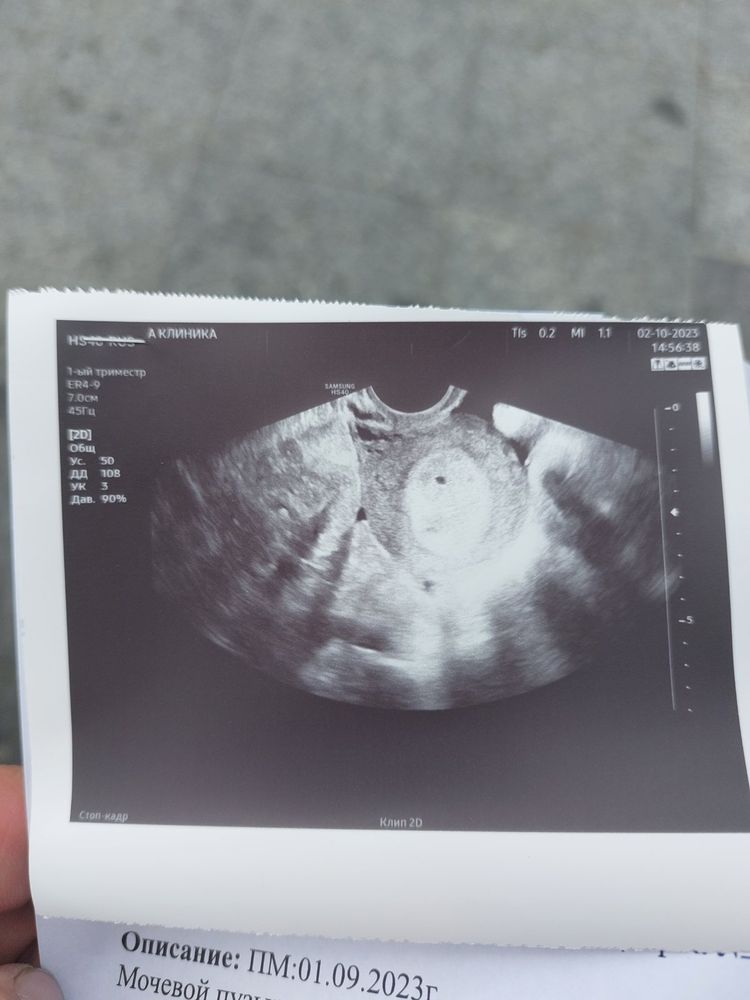

Kukla . kom, у вас там написано множество включений диаметром 3 мм,это не то,когда видно пя четко пишут диаметр пя и указывают срок,а у вас все под вопросом,потому что какой смысл узи так рано делать,вот моё УЗИ в 5 недель акушерских Изображение

Марина, у меня 5 недель